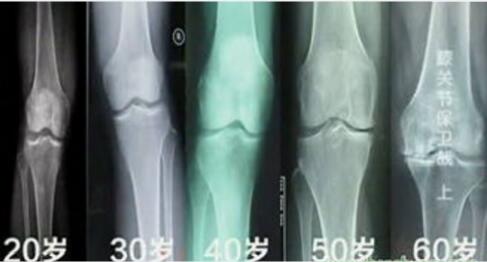

30岁以前:膝关节处于从成长到初生的“完美状态”;30-50岁:膝关节的各软骨和半月板等部位开始出现轻度的磨损和病变;50岁以上:膝关节内的软骨、半月板出现老化,关节周围的肌肉、韧带萎缩使得对膝关节的保护能力减弱。

特别是男性60岁、女性50岁以后,其生理功能退化,关节腔内的润滑物质减少,软骨磨损变薄,失去弹性,造成骨头之间彼此摩擦发炎,引发疼痛。